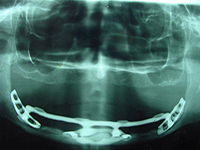

| Figure 1: Subperiosteal design dental implants | ||

Commercial dental implants came to the United States in 1940 with Gustavo Dahl presenting the first dental implants—a subperiosteal design (Figure 1). Dental implants have undergone various transformations in design, shape architecture, and metallurgy or component constituency. Currently, hundreds of different designs and components exist. Since their inception in 1940, implants have changed from the subperiosteal design to blade-type or endosteal implants invented by Dr. Leonard Linkow of New York (Figure 2), to modern screw-type implants (Figure 3) and mini implants (Figure 4), with each type promoting different restorative options in the field of dental implantology. All of these, when located in unknown remains, can provide a useful tool for the forensic dentist as a possible piece of the puzzle in the identification protocol.